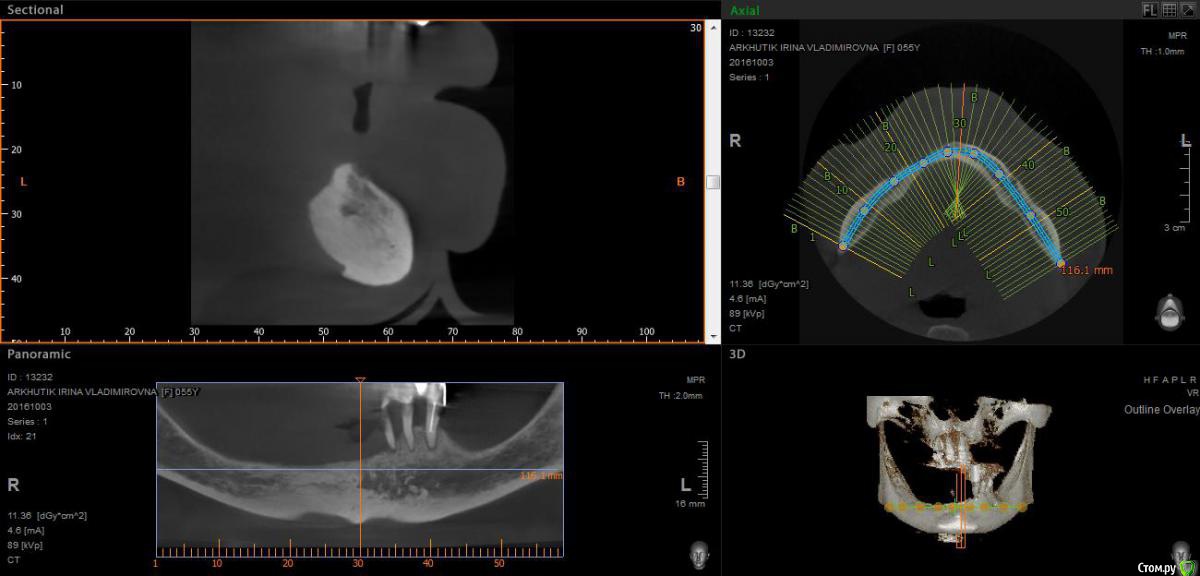

Rusty Опубликовано 5 октября, 2016 Поделиться Опубликовано 5 октября, 2016 Добрый день. К ортопеду обратилась пациентка 55-60 лет с такой ситуацией. Пришла с дочкой, дочь с мамой настаивали на несьемной конструкции, ортопед отправил на кт и вот. Не хочу планировать ей много хирургии, оцените и мой план пожалуйста и буду рад услышать советы по реабилитации пациента. По сути да) просто искал место куда есть возможность поставить, ортопед говорит тогда балка либо локаторы Ссылка на комментарий

Nazim_NV86 Опубликовано 5 октября, 2016 Поделиться Опубликовано 5 октября, 2016 На н/ч балка? Какие измерения в дист отделах? На в/ч мало четырёх. По три бы. Ссылка на комментарий

Rusty Опубликовано 5 октября, 2016 Автор Поделиться Опубликовано 5 октября, 2016 На н/ч балка? Какие измерения в дист отделах? На в/ч мало четырёх. По три бы.На н/ч балка, в дистальных отделах над каналом около 3мм. На вч условий для установки больше 4 не нашел) Ссылка на комментарий